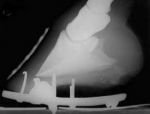

Dotaz 1: Dokážete popsat, co je na těchto zadních kopytech špatně? Odhadnete, jak bude uložená v levém zadním kopytě kopytní kost?Odpověď, obr. 1: Tato zadní kopyta mají podsunuté patky a příliš dlouhou špici, je na nich vidět tzv. „buldočí nos", který je výraznější na levém kopytě. Na rentgenovém snímku tohoto kopyta lze vidět zřetelně, jak je kopytní kost naklopená dozadu (negativní palmární úhel).

Přestože obrázek 11 (vpravo) není kvalitní, lze na něm jasně vidět, jak strměji je nakloněná korunka oproti předchozím dvěma snímkům. Rentgen na obr. 1 potvrzuje teorii o souvislosti korunky s úhlem kopytní kosti tím, že ukazuje kopytní kost naklopenou dozadu.